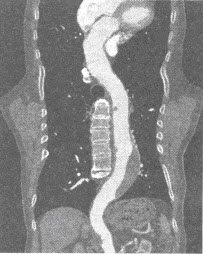

男,55岁。腹痛伴发热1周就诊。主动脉CTA检查MPR如图,考虑为()

A:主动脉夹层动脉瘤

B:主动脉瘤并附壁血栓

C:主动脉血栓形成

D:主动脉硬化

E:主动脉破裂